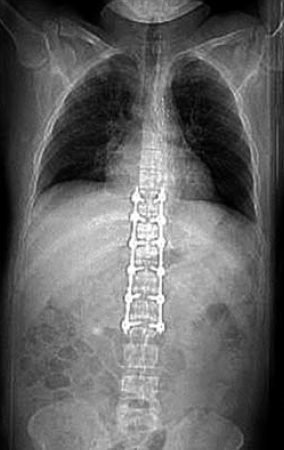

10. ábra.

A lumbalis gerinc rögzítése után az aorta laesio megoldását halasztottan végeztük.

11. ábra.

A stent graft beültetés során végzett DSA az aortasérülés okozta álaneurysmát mutatja.

12. ábra.

A stent graft beültetése után az aorta kontúrja kiegyenlített, az álaneurysma szájadéka lefedésre került.

Neurológiai vizsgálattal petyhüdt alsó végtagi paraplegia volt kimutatható. Tudata visszatért. 24 órán belül, keringési paramétereinek stabilizálása után, stent graft implantatiot, majd másnap ThX-LII segmentumban transpedicularis gerincrögzítést végeztünk (10.,11., 12. ábra). Paraplegia mellett lábszártörését egy héttel később lemezes osteosynthesissel oldottuk meg. A postoperativ szakban septicus szövődmények alakultak ki mind lágyrész sérüléseinek mind gerincműtétének területén. Hosszas antibiotikus kezelés mellett septicus állapota rendeződött. Parapareticus állapotban került vissza a beküldő kórházba rehabilitatio céljából. A betegek és ellátásuk adatainak összefoglalását I, II és III táblázat mutatja.